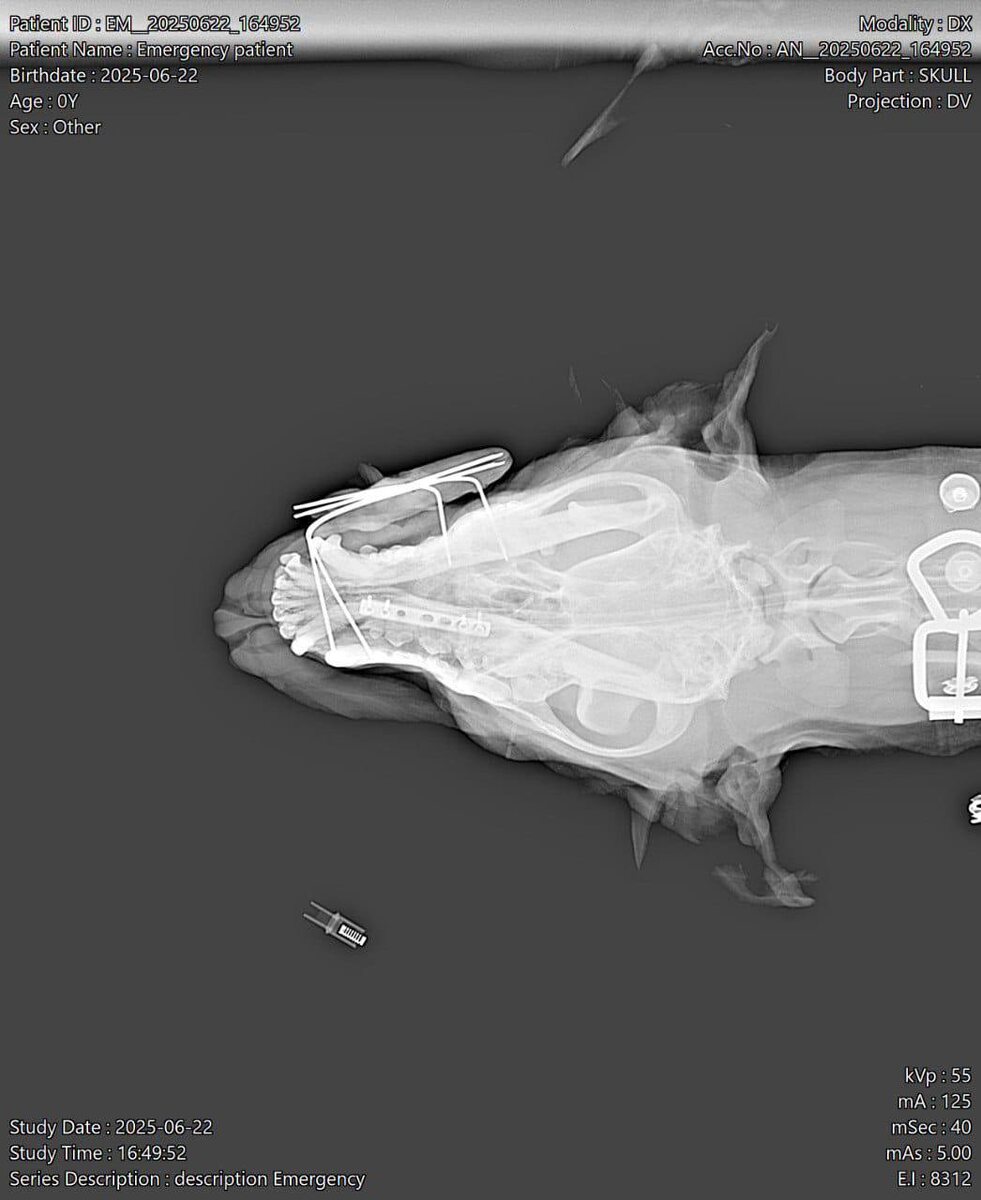

В наш филиал на Аверкиева, 24 поступила собака, в которую врезалась машина. Несмотря на серьёзность ситуации, она удивительно стойко держалась — была в сознании и даже вела себя спокойно.

Было принято решение: не теряя времени, провести операцию по лечению перелома.

Хирург Колисниченко Сергей Александрович успешно провёл вмешательство. Пёс перенёс наркоз хорошо и уехал в сознании, с надеждой на быстрое восстановление. 💪🩺